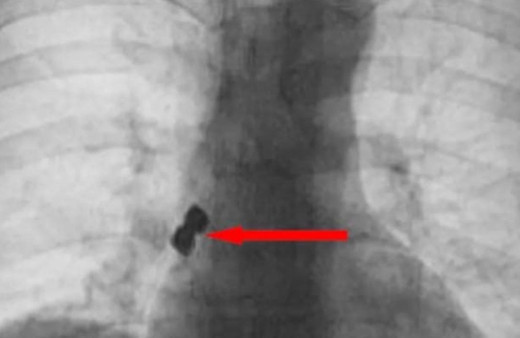

Diş Tedavisi